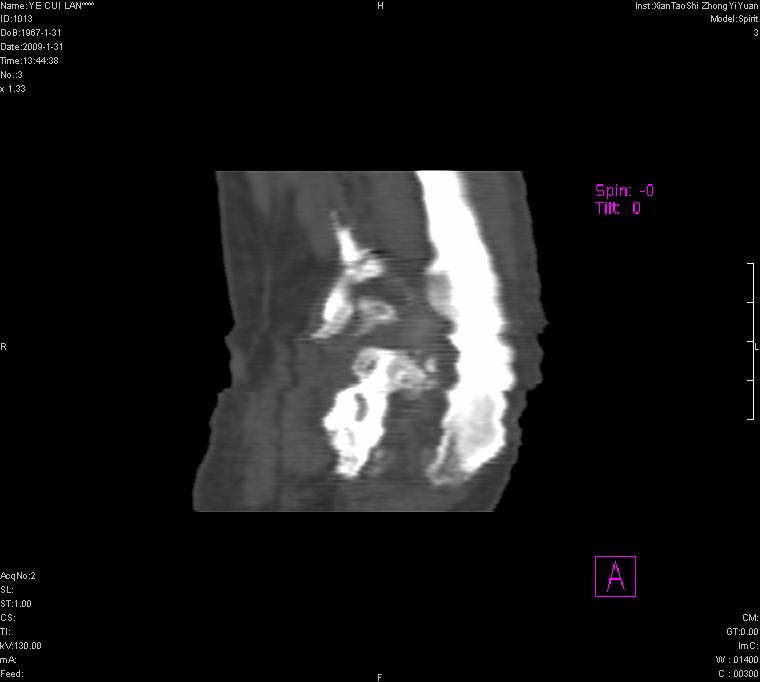

以下是引用王明发在2009-2-9 11:53:00的发言:[br]支持夏科氏关节,必要时行脊髓mri检查 [br]夏科氏关节是指由于某些神经系统疾病引起的关节病变,也被称为神经性关节炎。常见病因有脊髓痨、脊髓空洞症等。原发的神经病变可以造成关节深部感觉障碍,对于关节的震荡、磨损、挤压、劳倦不能察觉因而也不能自主地保护和避免,而神经营养障碍又可使修复能力低下,使病人在无感觉状态下造成了关节软骨的磨损和破坏,关节囊和韧带松弛无力,易形成关节脱位和连枷关节。关节面的破坏和骨赘的脱落变成关节内游离体。关节外形饱满肿胀,内有出血和渗出。这种病早期并无疼痛,不易被病人重视,仅表现为关节肿胀、无力、活动过度、动摇不稳。关节肿胀、无痛、活动范围超常是本病的重要特征。x光片可见有关节骨端广泛破坏、硬化或呈奇异形态,骨赘形成,关节间隙不规则或增宽,周围软组织钙化、关节内游离体、骨碎片等。结合x光片及临床症状,病人又有神经系统原发病症,即可确诊

以下是引用hhcckk在2009-2-9 14:31:00的发言:[br]夏科关节的六大表现[br]1.关节软组织肿胀。[br]2.关节的脱位与半脱位。[br]3.关节内的游离体。[br]4.关节面硬化,新骨形成。[br]5.骨质萎缩与破坏。[br]6.关节结构的紊乱。[br]加上患者无明显疼痛,诊断的把握性比较大